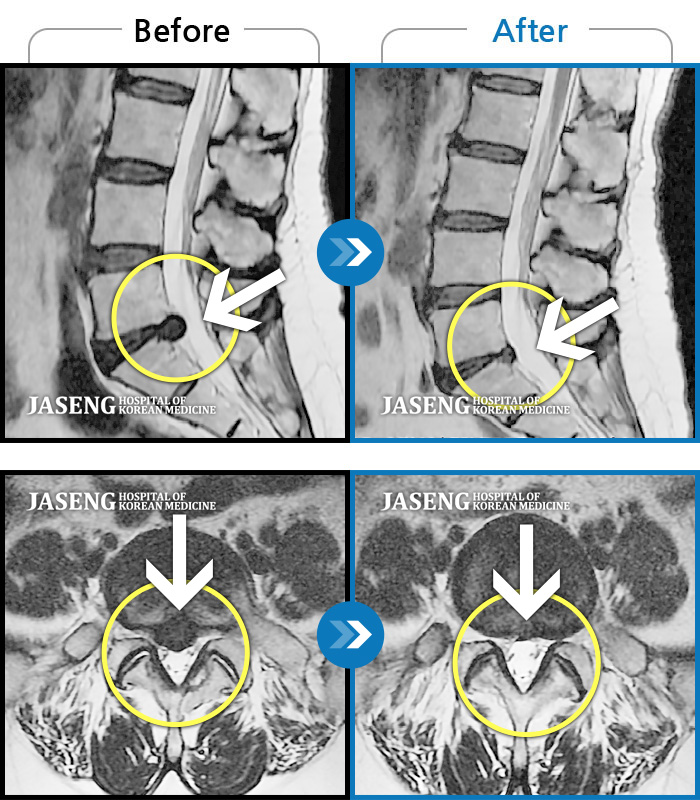

허리디스크

잠실 · 한상욱 원장

허리가 많이 아프고 왼쪽 다리가 저려 움직이기가 힘들다.

촬영시기

2022.01.19 ~ 2022.11.14

2022.12.02